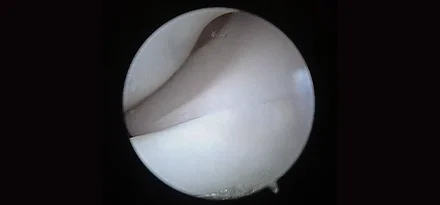

관절경 팔꿈치관절(Elbow) 확인

관절경 무릎관절(Stifle) 확인 (반월판 및 십자인대)

* 리본동물의료센터 케이스 사진으로 무단 복제 및 도용을 금지합니다.